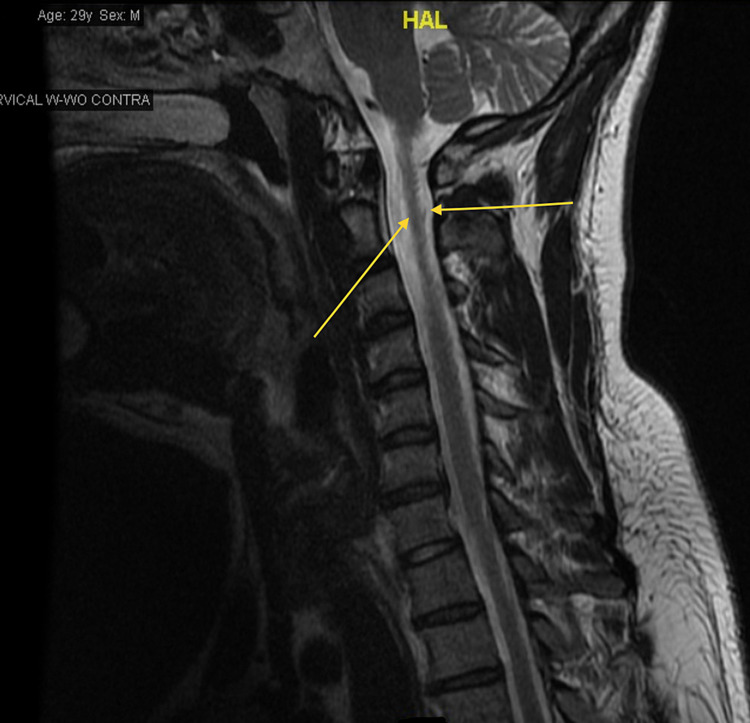

Throughout his hospital stay, his vitals were within normal limits. On physical examination, strength was preserved in all four extremities. His gait was observed to be without overt abnormalities, however, he endorsed a lack of awareness of his limbs’ movements in space. There were no signs of hyperpigmentation over the over knuckles or MTP joints, Romberg’s sign was negative and no ataxia in gait. Laboratory findings showed hemoglobin (Hgb) A1c of 5.1 (3.8%-5.6%), calcium 9.5 (8.4-10.2 mg/dL), C-reactive protein <0.50 (0-0.99 mg/dL), Vitamin B12 166 (239-931 pg/mL), folate 11.0 (2.76-20.0 ng/mL), thyroid-stimulating hormone (TSH) 5.79 (0.465-4.68 µIU/mL), and free T4 0.88 (0.78-2.19 ng/dL). Complete blood count (CBC) showed Hgb 15.4 (14.0-16.4 g/dL), Hct 45.6 (40.0%-47.2%), mean corpuscular volume (MCV) 101.8 (81.8-94.6 fL), and erythrocyte sedimentation rate (ESR) 1.0 (0-15 mm/hr). Multiplanar multi-sequence magnetic resonance imaging (MRI) of the cervical spine was performed both before and after the administration of intravenous contrast. The cervical spine MRI revealed dorsal cord signal abnormalities without enhancement in a pattern consistent with vitamin B12 deficiency (Figure 1).